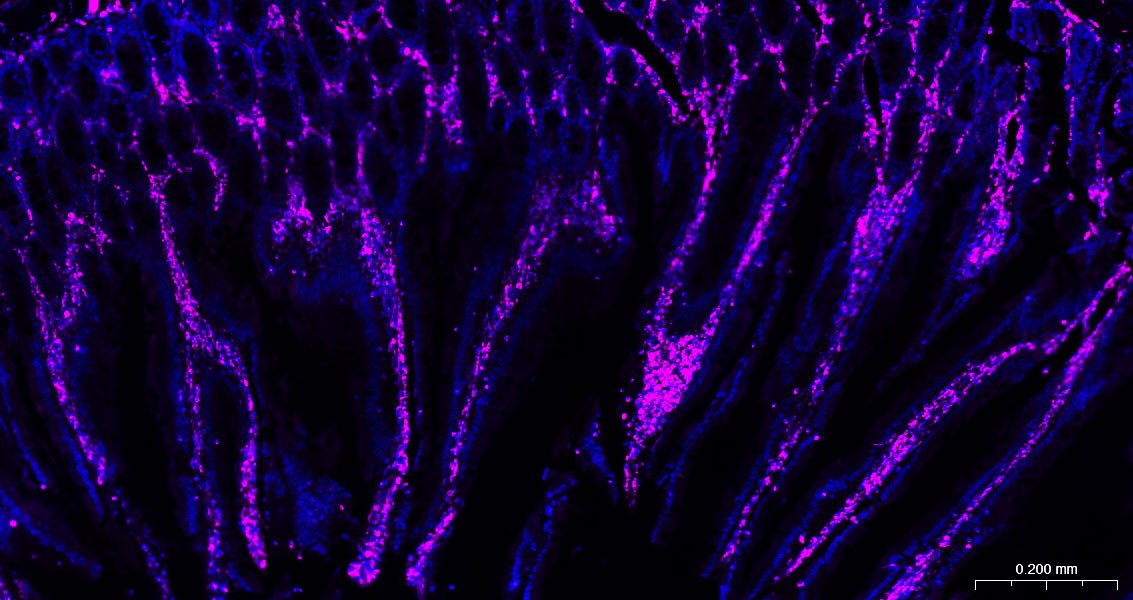

28. Paraformaldehyde-fixed, paraffin embedded Rat Kidney; Antigen retrieval by boiling in sodium citrate buffer (pH6.0) for 15 min; The section was incubated with Vimentin Polyclonal Antibody, Unconjugated (TMAB-01966) at 1:200 overnight at 4°C. Followed by conjugated Goat Anti-Rabbit IgG antibody (Rose Red), DAPI (blue) was used to stain the cell nucleus.

29. Paraformaldehyde-fixed, paraffin embedded Mouse Kidney; Antigen retrieval by boiling in sodium citrate buffer (pH6.0) for 15 min; The section was incubated with Vimentin Polyclonal Antibody, Unconjugated (TMAB-01966) at 1:200 overnight at 4°C. Followed by conjugated Goat Anti-Rabbit IgG antibody (Rose Red), DAPI (blue) was used to stain the cell nucleus.

30. Paraformaldehyde-fixed, paraffin embedded Human Kidney; Antigen retrieval by boiling in sodium citrate buffer (pH6.0) for 15 min; The section was incubated with Vimentin Polyclonal Antibody, Unconjugated (TMAB-01966) at 1:200 overnight at 4°C. Followed by conjugated Goat Anti-Rabbit IgG antibody (Rose Red), DAPI (blue) was used to stain the cell nucleus.

31. Paraformaldehyde-fixed, paraffin embedded Rat Small Intestine; Antigen retrieval by boiling in sodium citrate buffer (pH6.0) for 15 min; The section was incubated with Vimentin Polyclonal Antibody, Unconjugated (TMAB-01966) at 1:200 overnight at 4°C. Followed by conjugated Goat Anti-Rabbit IgG antibody (Rose Red), DAPI (blue) was used to stain the cell nucleus.

32. Paraformaldehyde-fixed, paraffin embedded Mouse Small Intestine; Antigen retrieval by boiling in sodium citrate buffer (pH6.0) for 15 min; The section was incubated with Vimentin Polyclonal Antibody, Unconjugated (TMAB-01966) at 1:200 overnight at 4°C. Followed by conjugated Goat Anti-Rabbit IgG antibody (Rose Red), DAPI (blue) was used to stain the cell nucleus.